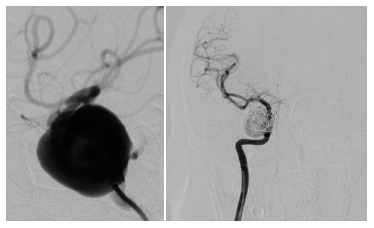

56岁的李女士来自湖南邵阳 , 近日因“突发视力下降、视野缺损”就诊于当地医院 , 完善相关检查后发现“右侧海绵窦窦段巨大动脉瘤 , 颈内动脉海绵窦段受压变细并有移位” , 动脉瘤直径达28mm,因动脉瘤巨大 , 动脉瘤颈位于海绵窦内很大的增加了外科手术的困难;考虑一旦破裂出血 , 难以止血 , 病死率高 , 遂转诊至湖南省第二人民医院(湖南省脑科医院) 。

李女士入院后 , 进一步行脑血管造影检查 , 明确了李女士动脉瘤大小、形态及位置 , 因李女士动脉瘤的位置特殊 , 开颅夹闭动脉瘤的方式并不合适;经科内讨论及与李女士商议后采用了微创的介入治疗方式 。

刘坤主任医师介绍 , 手术主要是在右侧腹股沟区(右腿根部)穿刺股动脉置入一根股动脉鞘 , 然后微导管将特殊的支架(管型网状结构)覆盖在血管薄弱长动脉瘤的区域 , 加固血管壁 , 让血液顺着管道往前方流动 , 减少对血管壁的冲击 , 从而使动脉瘤内血流减少 , 再往动脉瘤内放置少许弹簧圈 , 促进动脉瘤内血栓形成 , 从而极大的降低了动脉瘤的破裂风险 , 促进血管壁的自我愈合 。